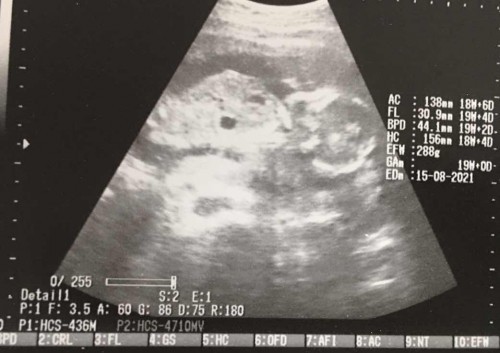

เนื้องอกในมดลูก

อัลตราซาวด์วันนี้พบว่าตัวเองเป็นเนื้องอก5ซม. ตกกลางคืนมาน้ำคล่ำแตก ตอนนี้น้องไม่อยู่แล้ว ใจสลายทุกอย่างเกิดขึ้นเร็วไปหมด

ตอนที่น้องเสีย18สัปดาห์ค่ะ